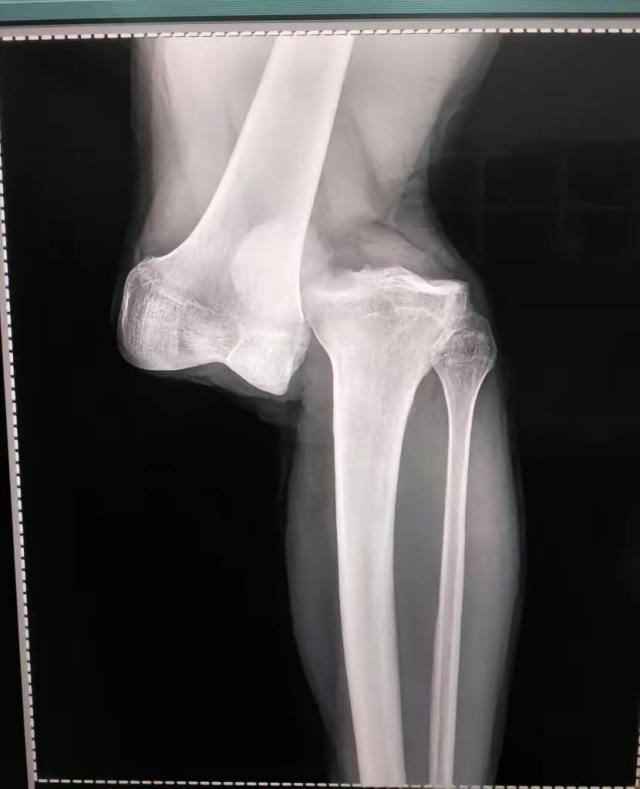

8月2日,做过检查,住院观察一夜之后,卢西亚诺·桑切斯坐着轮椅出了院。他的左膝脱了臼,大腿骨和腓骨分开了,三周之内做手术,可能一次手术还不行,得做多次手术,至少需要休息10个月,甚至有可能是1年。

8月2日接受阿根廷一电台采访,阿根廷青年人俱乐部队医亚历杭德罗·隆科罗尼说:“做了23年医生,我从没见过这么严重的伤病。(阿根廷队队医比利尼)干了40年医生,他对我说他也没见过一样的伤病。是膝盖完全脱臼。大腿骨和腓骨基本上分离了。前后十字韧带都撕裂了,我们还得看半月板情况怎样。”

下面是卢西亚诺·桑切斯受伤瞬间照片、在医院病床上拍的腿部照片以及X光检查结果,画面比较强烈,请谨慎考虑是否观看:

X光片